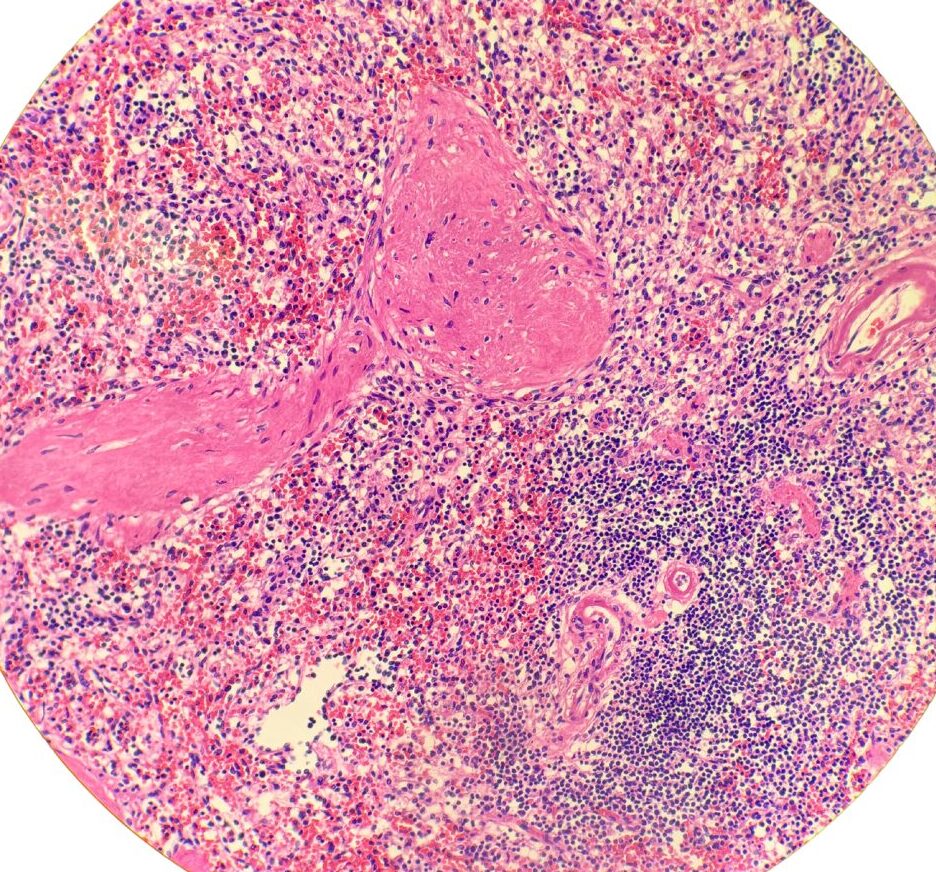

PAS反応標本(別冊No.9)を別に示す。

出典;厚生労働省ホームページ

第71回臨床検査技師国家試験の問題および正答について午前問題別冊

3

【この問題のポイント】

この問題は、PAS反応(Periodic acid–Schiff反応)で染まる構造と、画像に見える組織構築から臓器を判定する問題。

PAS反応は多糖類(グリコーゲン)、中性ムコ多糖、糖タンパク、基底膜成分などを赤紫色に染める。

腎臓では糸球体係蹄の基底膜などがPAS陽性となり、臓器同定に有用である。

腎小体を認識できるかどうかが鍵である。

またPAS反応の時点で腎臓、肝臓、食道、膣、大腸、胃などに絞られる。

3 腎臓

腎皮質では腎小体(糸球体とボーマン嚢からなる球状構造)と多数の尿細管がみられる。

PAS反応で糸球体基底膜などが陽性になる。

この所見が今回の画像(複数の腎小体+周囲に尿細管が密に存在)と一致する。